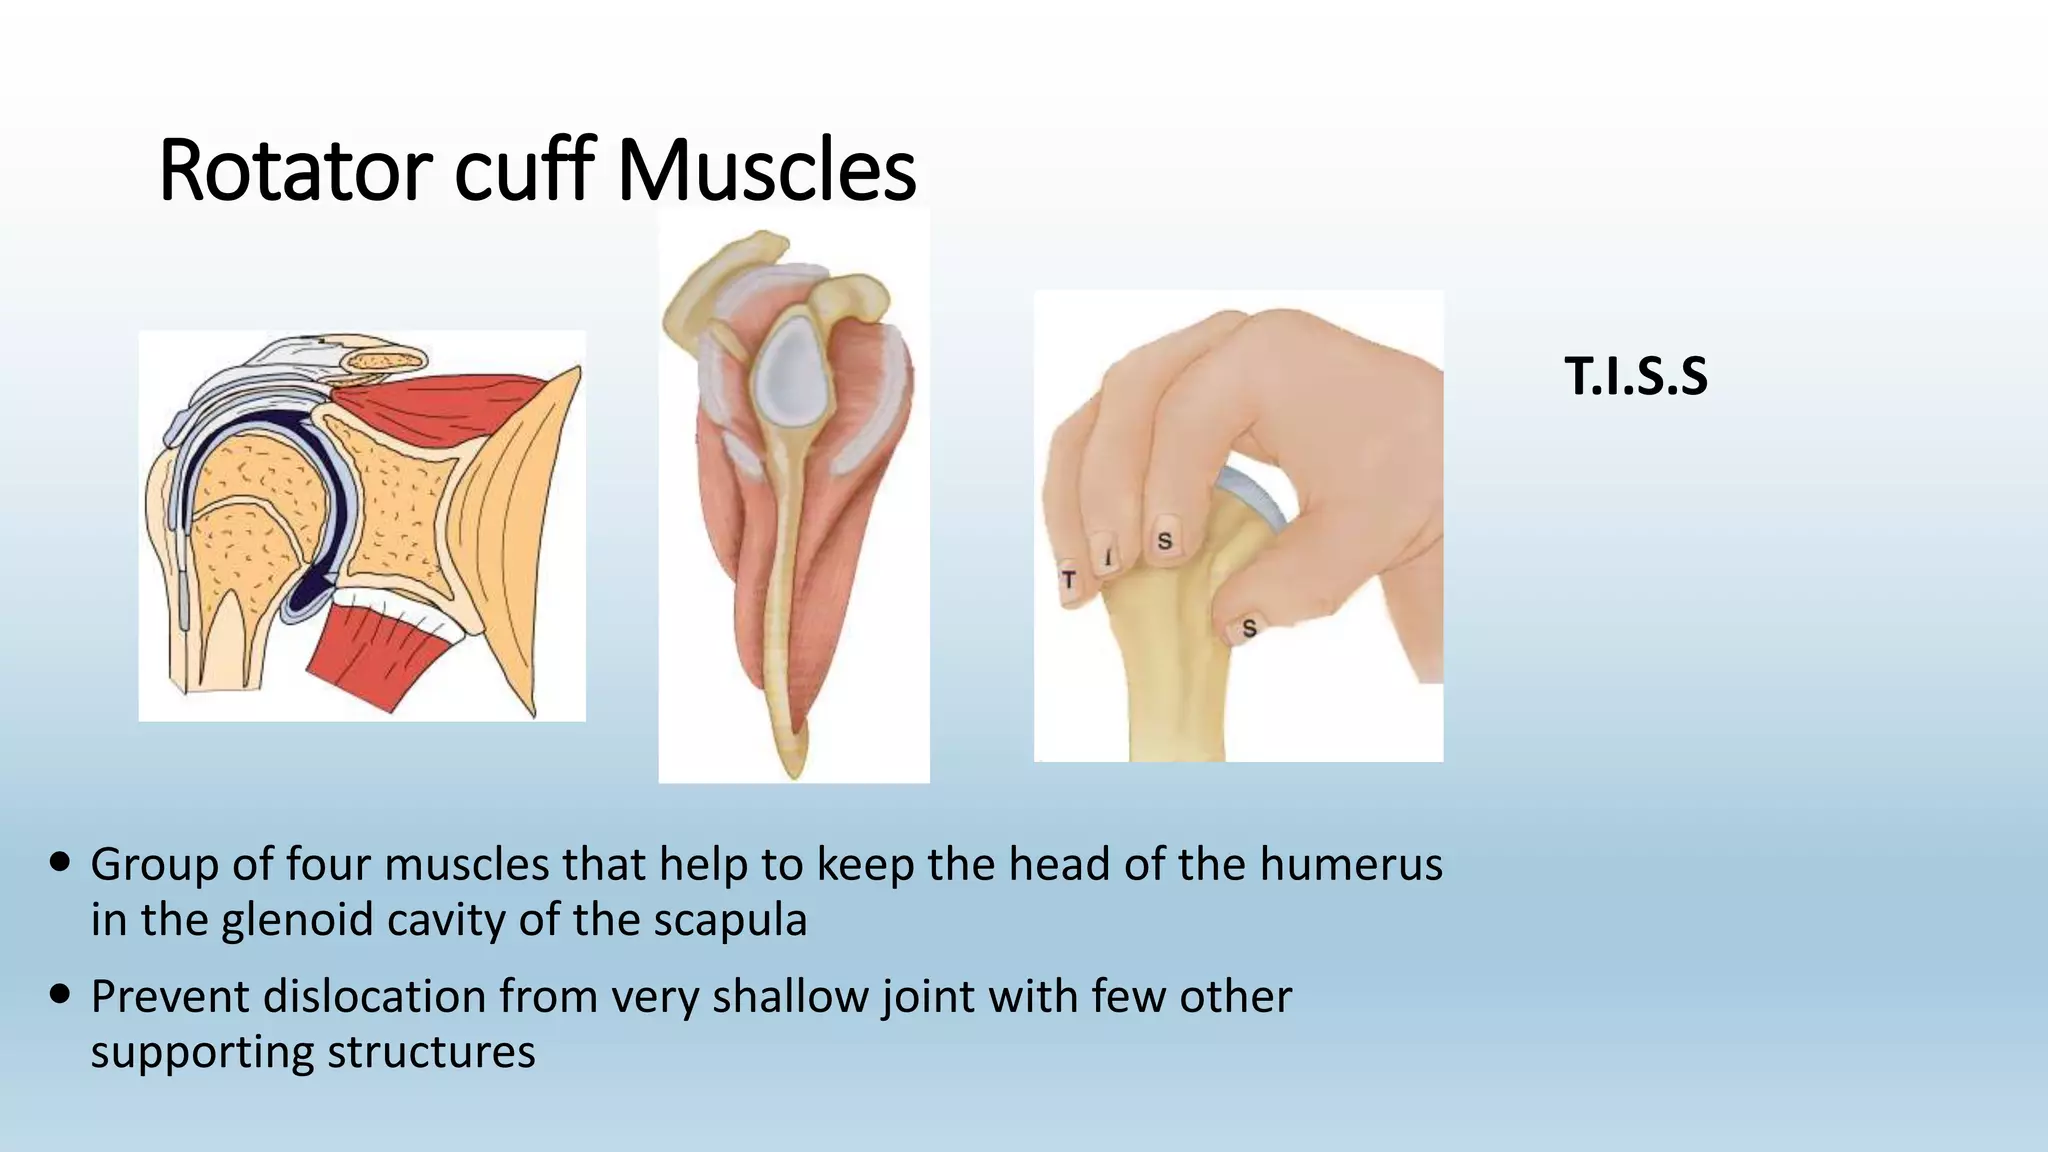

The document summarizes an anatomy revision session on the upper limb. It discusses various muscles of the upper limb including their origins, insertions, innervations and functions. Key muscles covered include the pectoralis major and minor, serratus anterior, deltoid, biceps brachii, brachialis, coracobrachialis, and triceps. It also discusses the rotator cuff muscles and muscles of the forearm including flexor carpi ulnaris and radialis. The session aims to help students identify upper limb muscles and understand their relations to nerves.